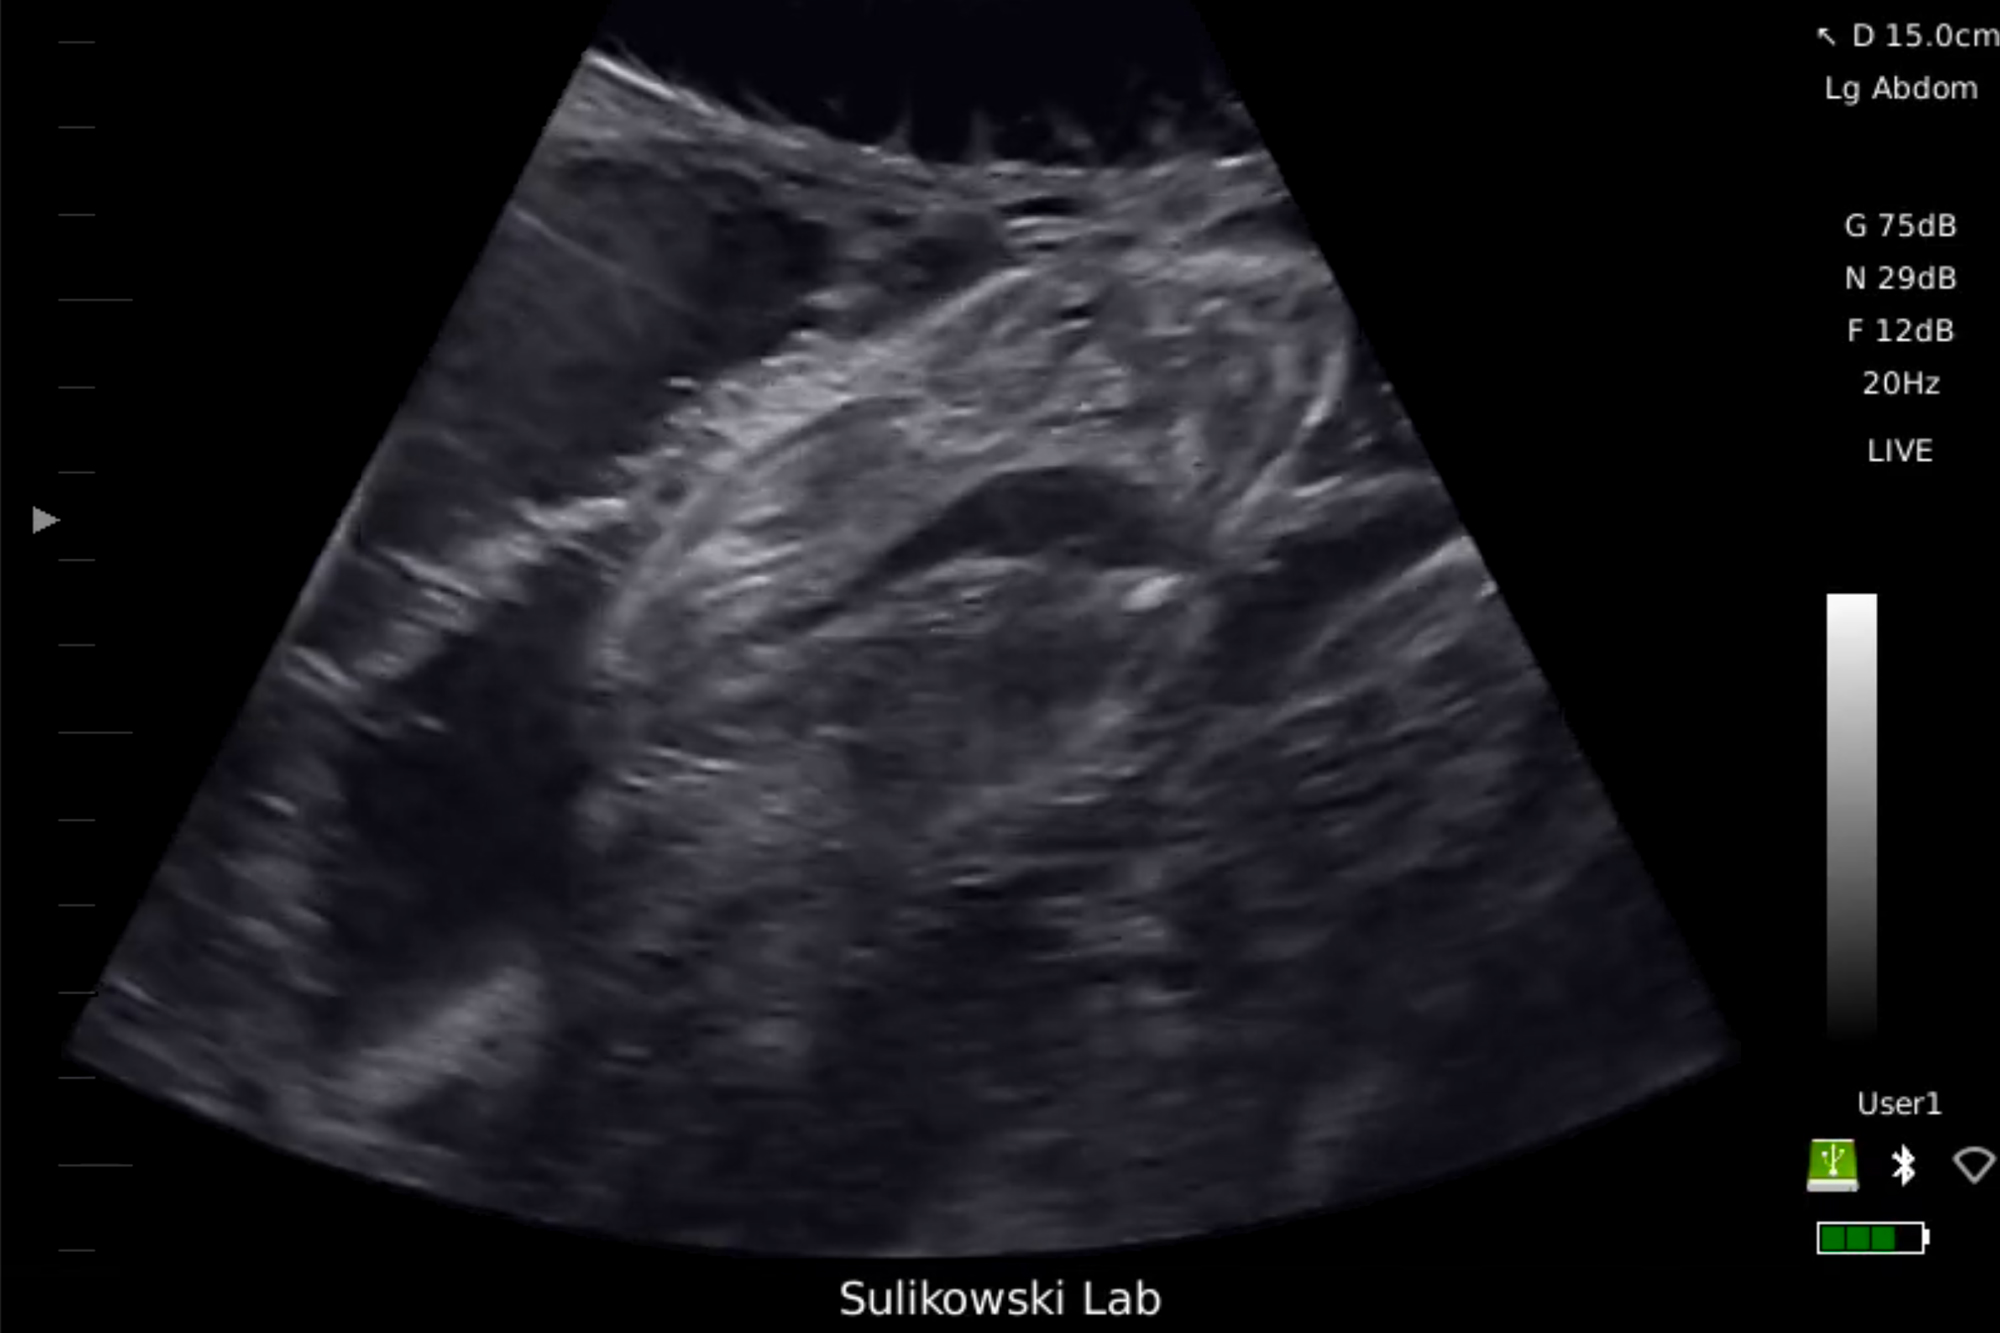

A not-so-routine ultrasound. Tanya Houppermans

Just like the ultrasounds used on humans, we use a mobile ultrasound machine to figure out if a shark is expecting. I put on a pair of goggles that allow me to see everything the ultrasound sees, lean over the side of the boat, and place the probe onto the upside down shark’s abdomen. The image is usually fuzzy at first as water splashes over the shark and up onto the boat. The team holds the shark still as I slowly maneuver the probe along her belly. Then, if she’s pregnant, something magical happens.

Wriggling baby tiger sharks, up to 40 of them packed tightly together inside their mother’s womb, appear in front of my eyes. The image also appears on a screen held by another team member on the boat, and everyone cheers as they gather around to take a peek into the secret world of unborn sharks. We spy on them as they pump fluid through their still-developing gills, and we watch in awe as they wiggle around, blissfully unaware that anything extraordinary is happening outside in the world. Once we have enough data on the approximate size of the offspring—which gives us an idea of how far along the pregnancy is—it’s time to tag the mama shark.

As I hold the probe as still as possible to keep a visual of the shark’s internal anatomy, Dr. Sulikowski takes the Birth-Tag and uses a custom-designed applicator to carefully insert it into the uterus through the urogenital opening. No surgery required, the tagging procedure is complete in a matter of minutes. Once the tag is inside the uterus, we rotate the shark upright to wake her and release her back to the open ocean. I am filled with hope as I watch her swim gracefully away to continue her pregnancy, with a stow-away Birth-Tag hidden among her unborn offspring.